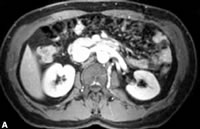

1例60岁男性患者左肾切除后发生急性肾功能衰竭,采用钆整合物进行增强MR显像示:A.术前两肾正常灌注;B.术后2天,患者发生急性缺血性肾衰竭。右肾示髓质灌注不良;皮质边缘灌注减低;C.随访3周显示,右肾灌注均匀,完全康复。